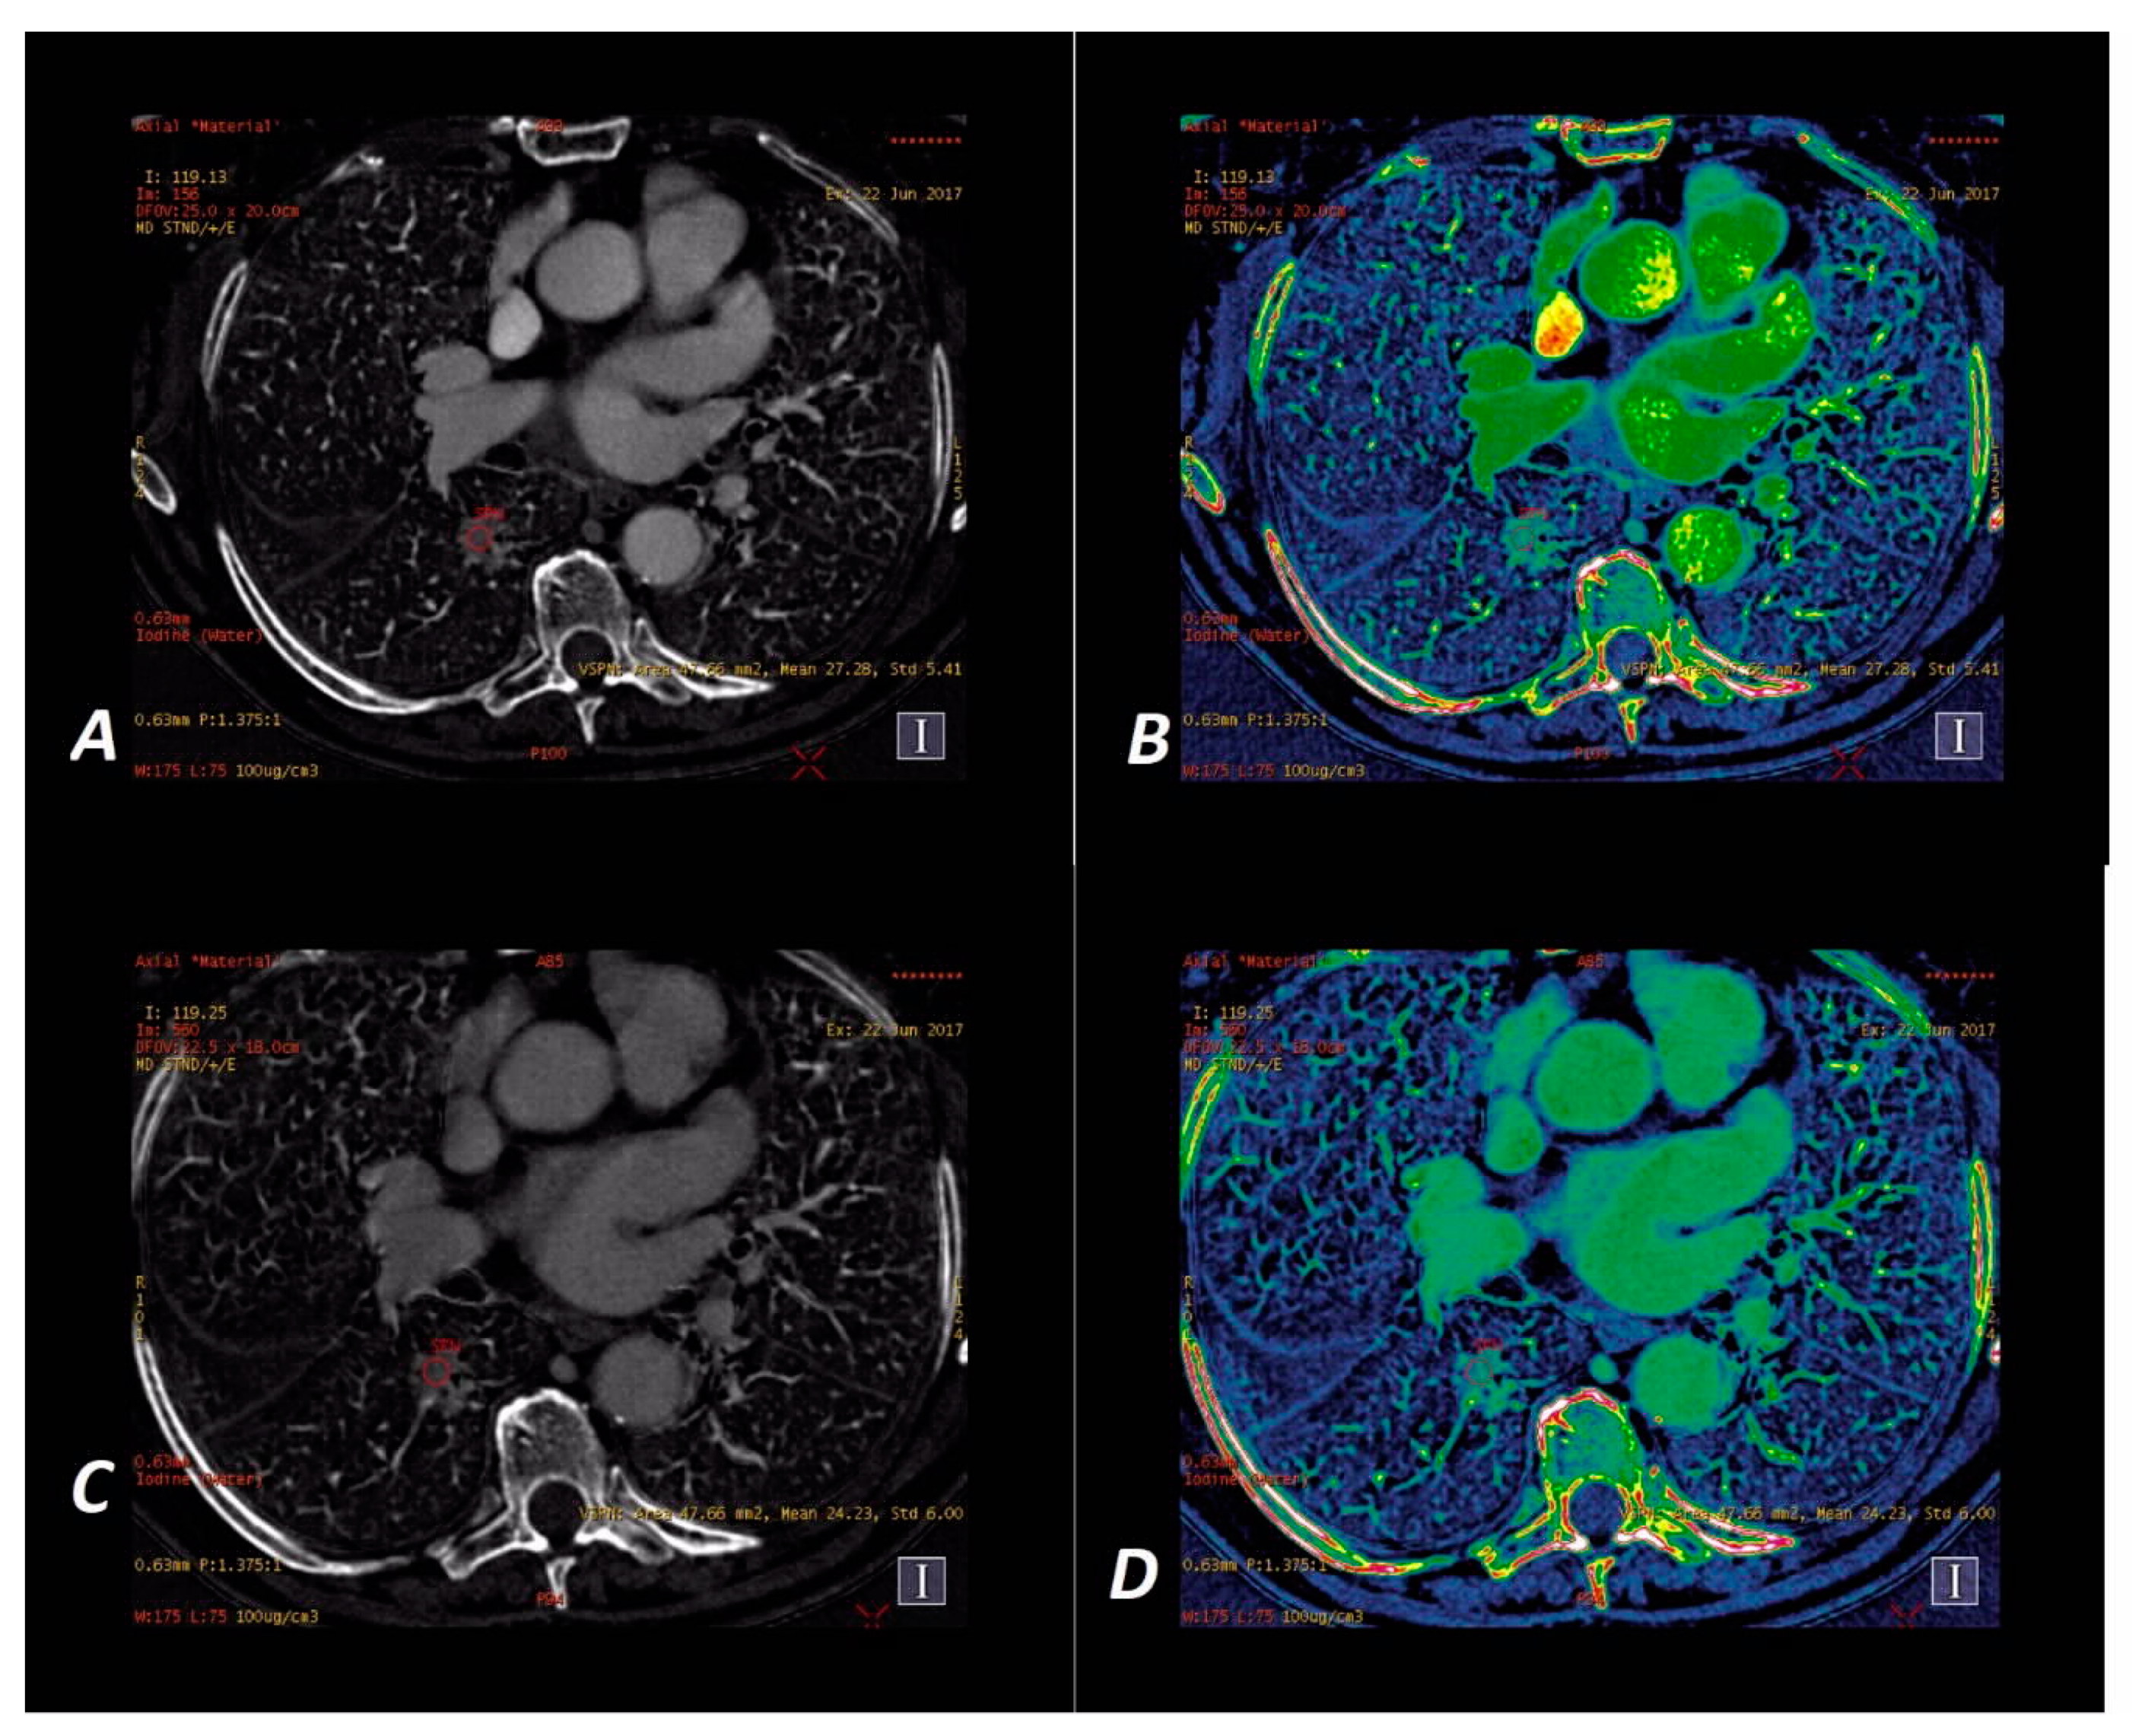

3.5. Results of the IC Map Analyses